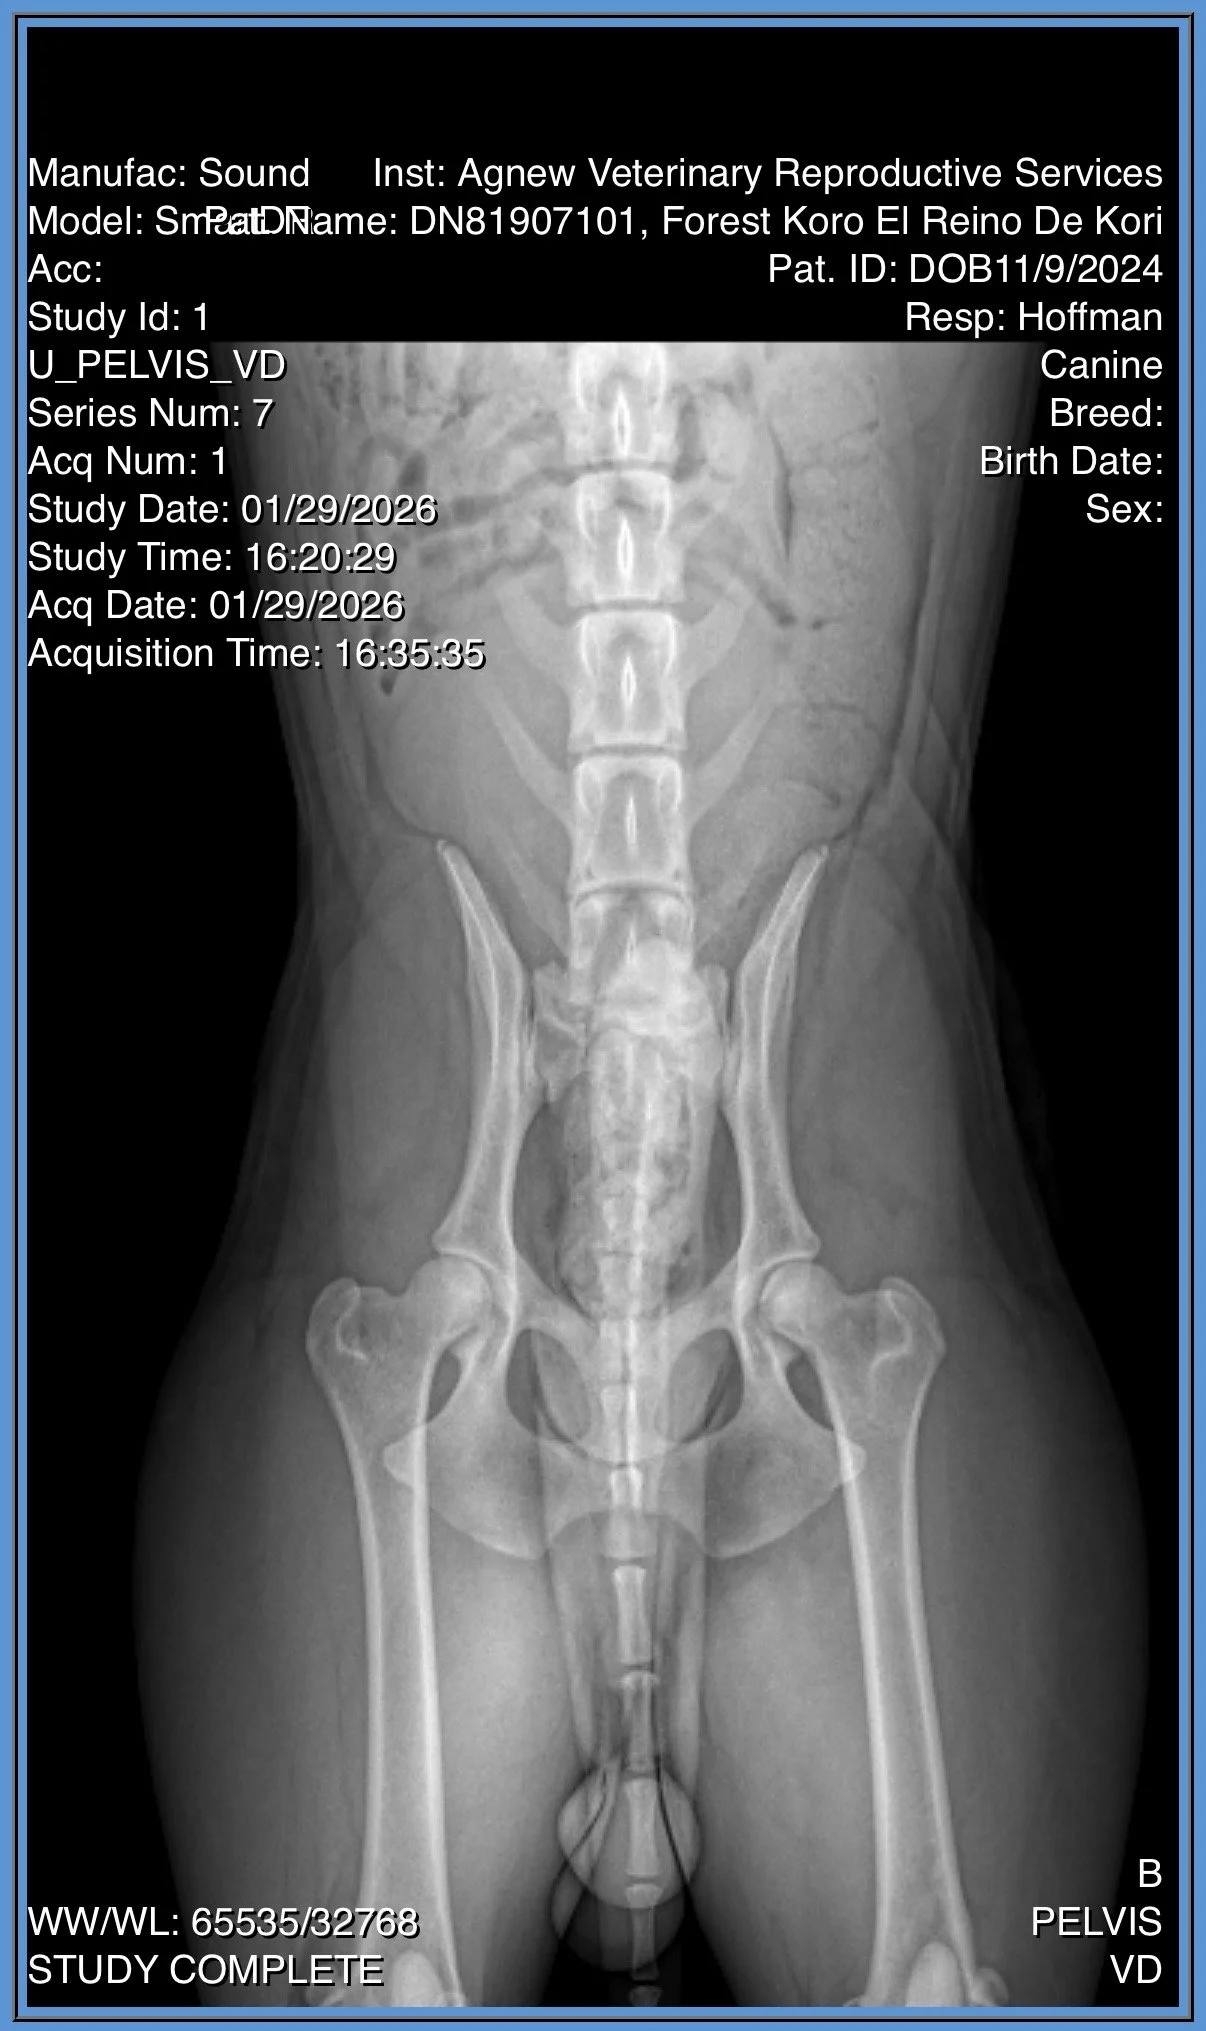

CH Forest Koro El Reino De Kori “Kpot”

Kpot was imported from Poland in 2025 from a kennel that focuses on conformation and agility. He is a sweet guy who earned his AKC championship at 9 months. Kpot was Winners Dog and BOS in puppy sweeps at the Mudi National 2025 and he is starting his agility journey and chipping away at his GCH!